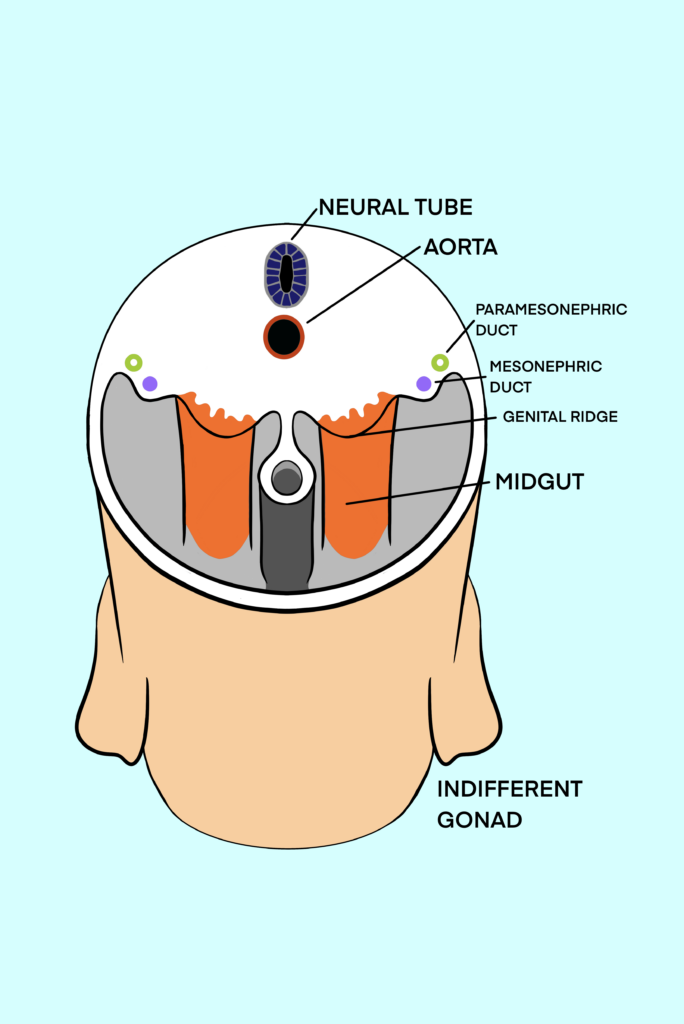

Traditional embryology education often oversimplifies genital system development, relying on binary models that fail to reflect biological diversity. Our interactive module addresses this gap, offering a comprehensive, research-backed exploration of genital development with a focus on inclusivity and scientific accuracy. This approach promotes a deeper understanding of human biology while preparing students for real-world healthcare scenarios that require both medical knowledge and empathy.

Developed over 14 months (September 2023 – November 2024), this project brought together a multidisciplinary team of students, faculty, and medical professionals. Using industry-standard tools such as Adobe Illustrator, Photoshop, Animate, and Articulate 360, we created anatomically accurate visuals and animations. The module follows Universal Design for Learning (UDL) principles and Mayer’s principles of multimedia learning, ensuring an accessible and effective educational experience.

Development of the Genital System

- Develop a comprehensive and inclusive wireframe for an educational module about the embryonic development of internal genitalia, that sets the foundation for future module development.

- Foster empathy and understanding by showcasing the biological diversity in genital system development.